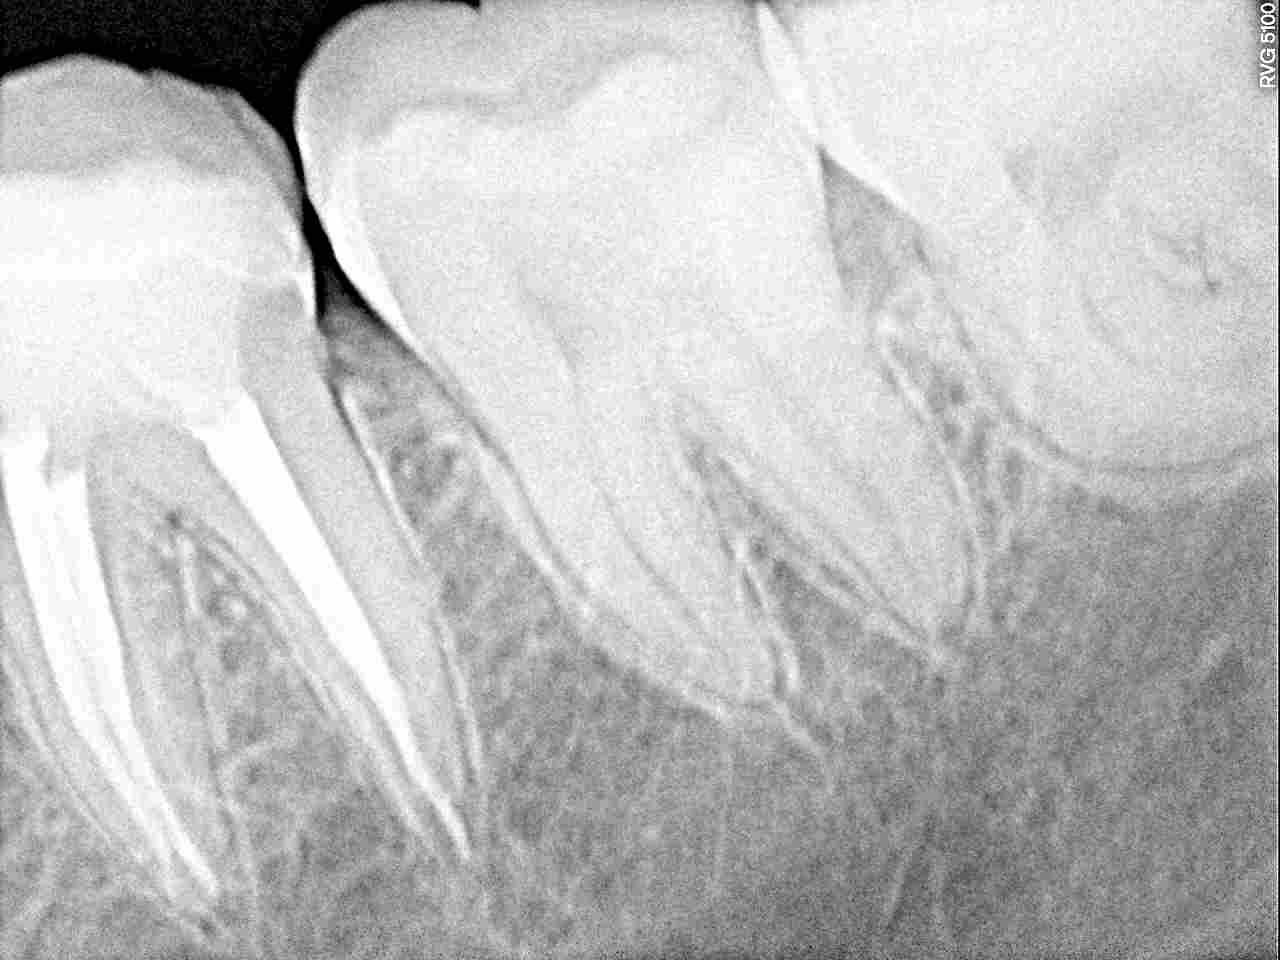

根充後のレントゲンになります

先までしっかりと薬を詰めています